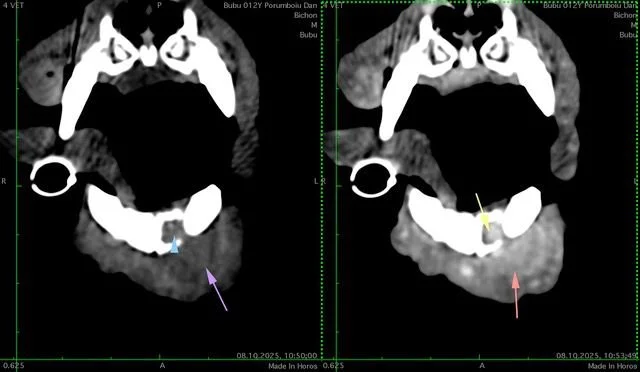

Bubu a ajuns la clinica QincyVet cu o formațiune vizibilă la nivelul mandibulei. La prima vedere, nu părea dureroasă, însă investigațiile au arătat că problema era mai serioasă decât părea.

• Tomografie computerizată (CT) - pentru a vedea cât de profund invadase formațiunea osul mandibular.

Rezultatele au arătat că formațiunea invadase osul mandibular, așa că s-a decis rezecția mandibulară parțială. Intervenția a fost una delicată, dar a decurs excelent.